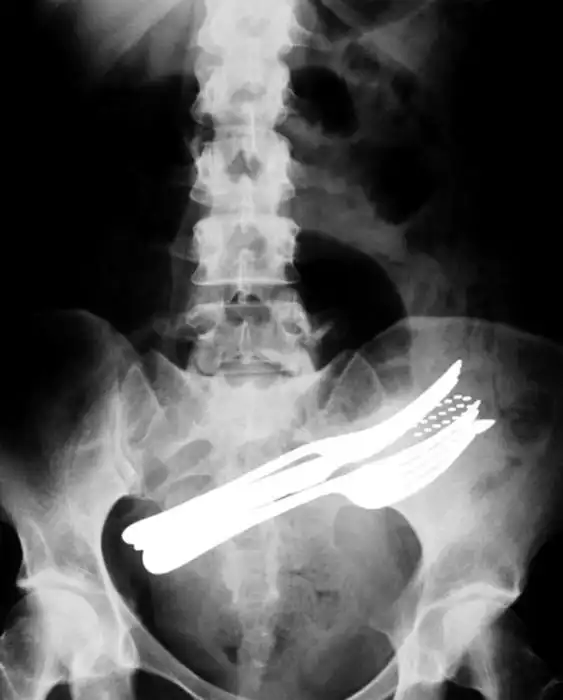

Порой даже не верится, с какими странными и необычными повреждениями в травматологию могут поступить пострадавшие. Всю эпичность профессии врачей травматологии могут с легкостью подтвердить рентгеновские снимки.